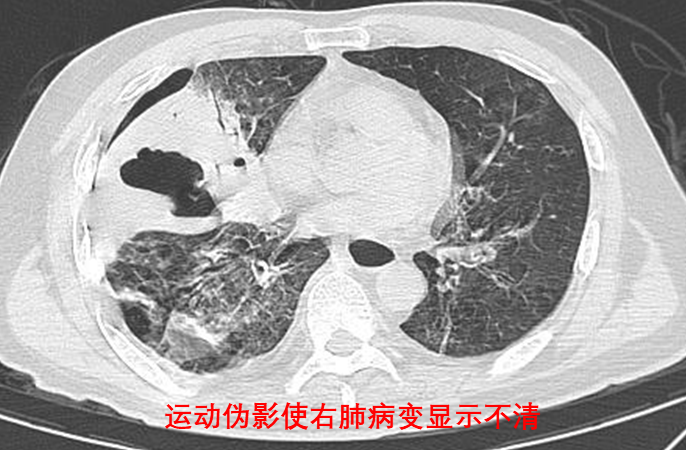

想象一下,如果你一边跑步一边拍照,照片上的人肯定会模糊不清。同样地,如果你在呼吸时拍胸部CT,肺部会因为呼吸而上下移动,这样拍出来的照片就会模糊或者有重叠的部分,医生就很难看清里面的情况了。

所以,憋气就是为了让你的肺部暂时“静止”下来,这样拍出来的照片就会更加清晰,医生就能更准确地看出你有没有问题了。